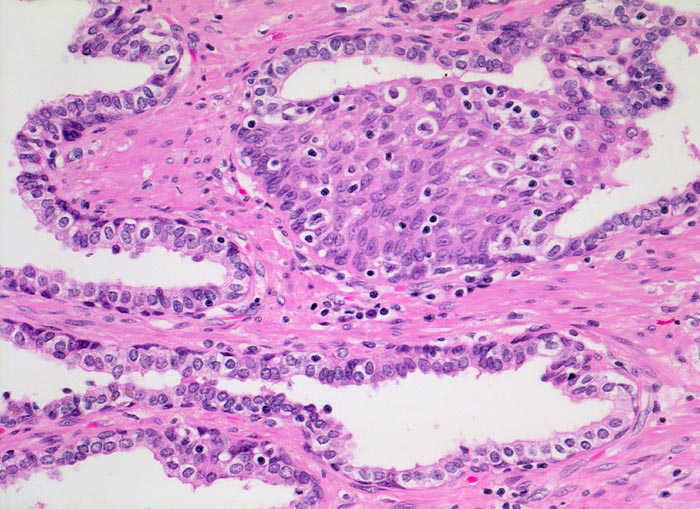

Morphologische Merkmale:

• Normale Prostatadrüsen mit grossen Lumina angeordnet in Läppchen. Das Epithel bildet Falten und besteht aus einer inneren hochprismatischen sekretorischen Zellschicht und einer äusseren Schicht flacher Myoepithelien.

• Herde kleiner Karzinomdrüsen ohne Basalzellschicht.

• Karzinomzellen mit stark erhöhter Kern-Zytoplasmarelation und hyperchromatischen Zellkernen mit grossen eosinophilen Nukleolen.